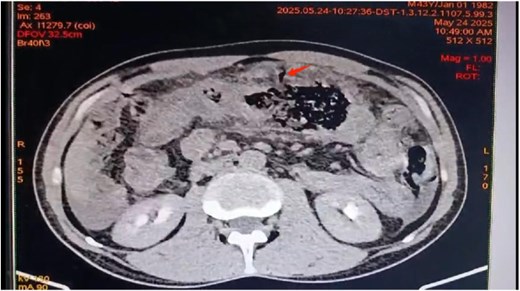

A contrast-enhanced abdominal CT showed Balthazar E pancreatitis with peripancreatic necrosis, thickening of the transverse colon and first jejunal loop, and sealed colonic perforation. Perisplenic and perihepatic fluid collections were noted, with no free air (Figs 1 and 2).

Axial view of contrast-enhanced abdominal CT scan revealing transverse colon wall thickening and a sealed transverse colon perforation.